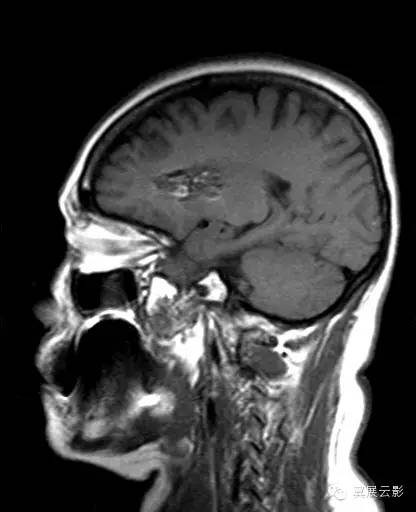

右侧基底节区可见不规则团片状混杂信号灶,累及右侧侧脑室前角,大小约15×34mm,边界尚清,呈爆米花样改变,T1WI等高信号,T2WI/FLAIR呈混杂稍高信号,边缘可见低信号环,无明显占位效应,DWI低信号。